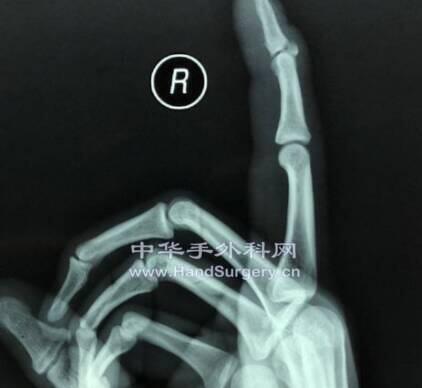

术前照片